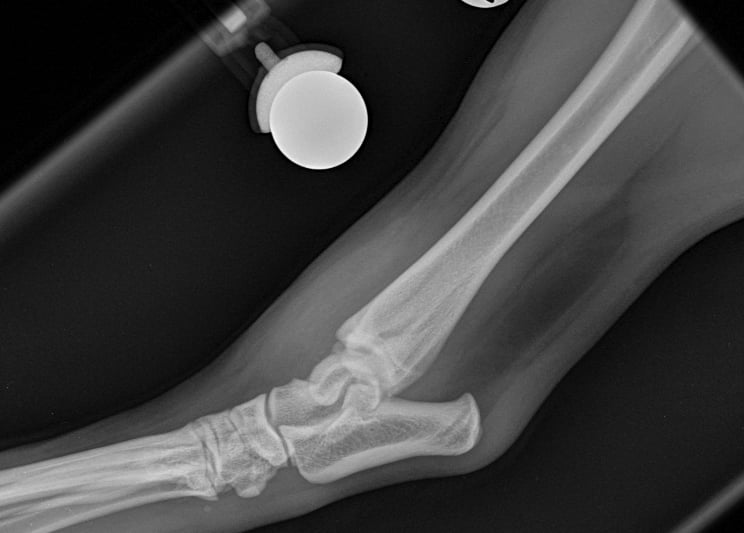

Lateral approach to the talocrural joint reveals severe oedema and bruising, 1.2mm IM pin placed in a distal to proximal fashion, 0.75mm cerclage wire used to create a figure-of-8 tension band. 1.4mm pin placed parallel to the talocrural joint from lateral to medial (Fig 3 and 4).

Fig. 3